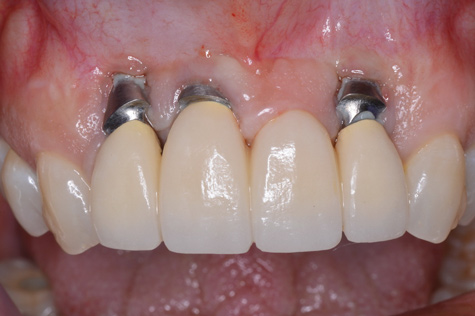

(11.) Implants placed too far towards the facial aspect of the ridge. With excessive pressure from the abutments and an ill-fitting prosthesis, implant therapy has failed. The facial bone is deficient, and there is significant mucosal recession and lack of keratinized tissue.

Figure 11

(12.) Implants placed too far towards the facial aspect of the ridge. With excessive pressure from the abutments and an ill-fitting prosthesis, implant therapy has failed. The facial bone is deficient, and there is significant mucosal recession and lack of keratinized tissue.

Figure 12